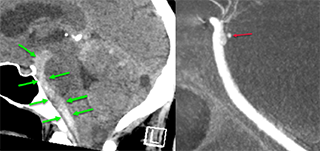

Extensive subarachnoid hemorrhage (green arrows) and the finding of a small perforator aneurysm (red arrow).

Perforator aneurysms of cerebral arteries  –  A possible Explanation of a common clinical problem?

Perimesencephalic subarachnoid hemorrhage (pmSAH) has long been considered a benign, non-aneurysmal entity. However, with the advent of high-resolution modern imaging, particularly advanced angiographic techniques, basilar artery perforator aneurysms (BAPAs) are increasingly recognized as an important and underdiagnosed cause in a relevant subset of patients. These hemorrhagic subtypes are associated with substantially higher complication rates and worse outcomes compared with truly non-aneurysmal pmSAH.